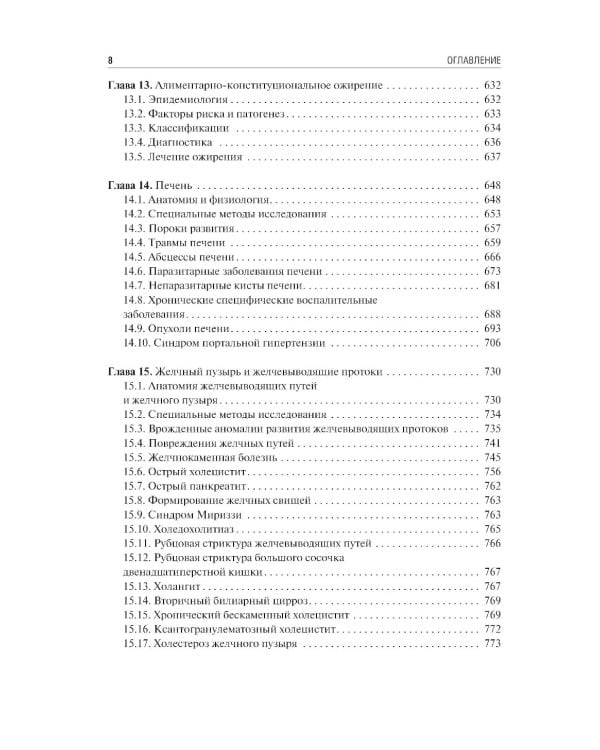

Содержание учебника соответствует программе по факультетской и госпитальной хирургии, а также квалификационной характеристике врача по специальности «Хирургические болезни» и включает главы по хирургической гастроэнтерологии, пульмонологии, кардиологии, ангиологии, флебологии и эндокринологии. В работе над ним принимали участие ведущие специалисты медицинских вузов, институтов РАН, клинических и научно-исследовательских центров. Издание предназначено для самостоятельной теоретической подготовки студентов старших курсов лечебного и педиатрического факультетов медицинских вузов, а также клинических ординаторов и аспирантов системы последипломного образования.| Издательство | ГЭОТАР-Медиа |